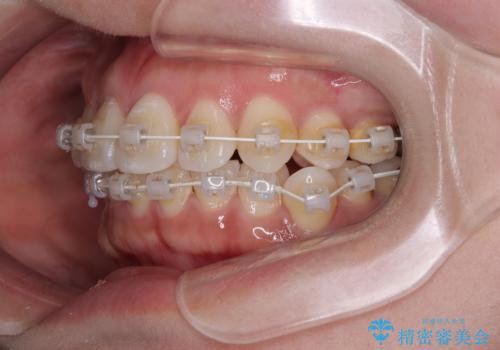

そこで本症例では、上顎右側にアンカースクリュー(矯正用インプラント)を埋入し、そこからゴムかけ(顎間ゴム)を行うことで、下顎の正中を右方向へコントロール。

これにより、左下小臼歯がく並ぶためのスペースを確保することができました。

矯正中の見た目にも配慮し、プラスチックブラケット+コーティングワイヤーの目立ちにくい審美装置を採用しました。